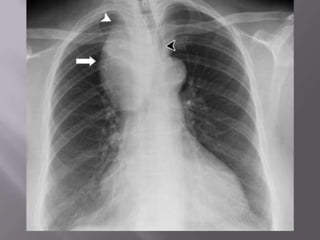

 Thymoma presenting on a chest radiograph

obtained before orthopaedic surgery in an

otherwise asymptomatic elderly female patient.

There is a large anterior mediastinal mass (A) with

coarse calcification visible on (B) the lateral view

and (C) contrast-enhanced CT.